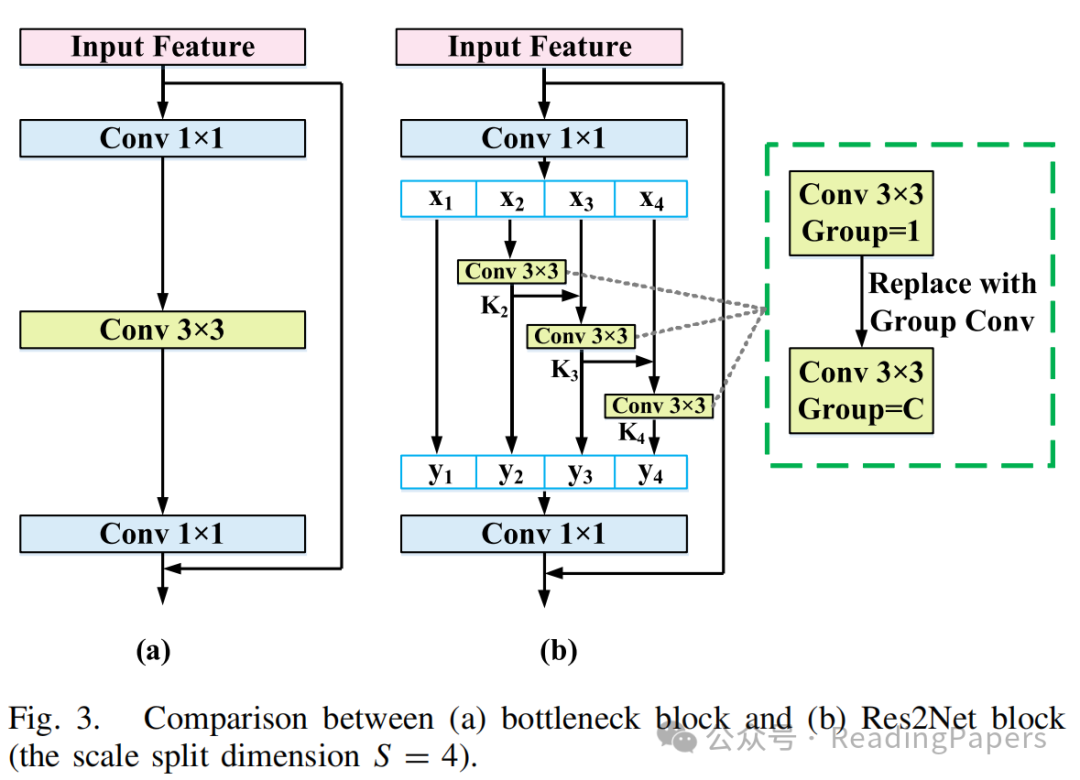

1) Res2Net50模型

标准的卷积核只能从给定图像中提取相同尺度的特征,因此需要构建不同大小的卷积核以获得多尺度特征。Gao等人提出了Res2Net,专门设计用于获取多尺度特征图。对于包括ResNet和ResNeXt在内的许多CNN架构,瓶颈块是基本组件。Res2Net寻求一种替代设计,以在保持与瓶颈块相当的计算负担的同时,获得更强大的多尺度特征提取能力。Res2Net块与瓶颈块的区别如图3所示。

具体来说,在1×1卷积之后,输入特征图被均匀地分为S个子集,表示为,其中。与输入特征图相比,每个子集具有相同的空间大小,但只有1/S的通道数。除了,每个对应一个3×3卷积操作符,表示为。的结果表示为。然后,与子集结合,并输入到中。因此,可以表示为: